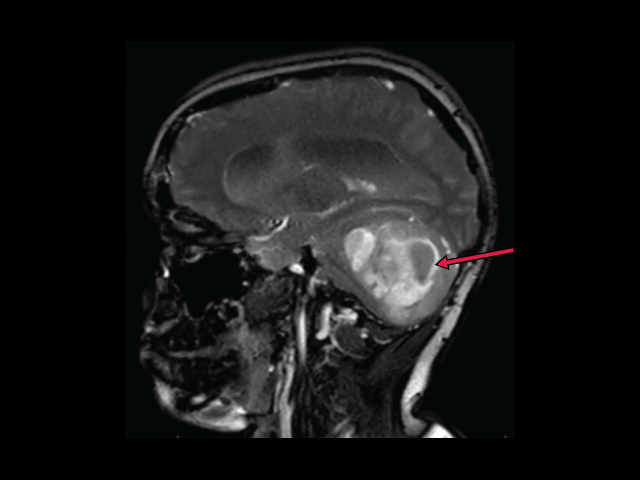

A low-grade but persistent brain tumor

At first glance, low-grade gliomas—which are the most common brain tumor in children—aren’t as aggressive as some other brain tumors, said Sadhana Jackson, M.D., of NCI’s Pediatric Oncology Branch, who was not involved with the study.

For example, unlike glioblastoma, which spreads rapidly and invasively into brain tissue, low-grade gliomas grow slowly and do their damage by pressing into nearby parts of the brain as they expand in size.

Depending on their location in the brain, some low-grade gliomas can be cured with surgery alone. But others, if they’re adjacent to sensitive structures in the brain, can’t be totally removed, Dr. Jackson explained.